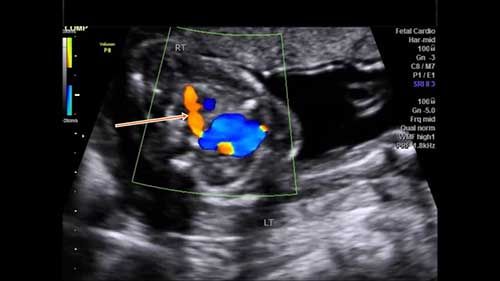

This 18-week fetus has a vascular anomaly. Can you identify it?